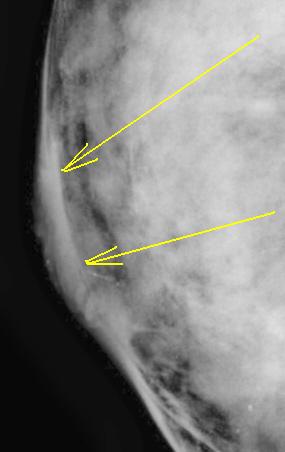

Имеется вопрос. Округлое просветление, помеченное желтыми стрелками - это, что кистозное образование? Какой, по Вашему мнению, морфологический субстрат этого просветления.

При анализе микрокальцинатов - красными стрелками помечены линейные кальцинаты, зелеными - древовидные кальцинаты, сиреневыми стрелками помечены "точечные" кальцинаты". Как Вы считаете, имеет ли диагностическую ценность форма и величина микрокальцинатов?

я читаю,что указанное желтыми стрелками овальное " обазование"-жировая долька,не думаю,что имеет место кистозный компонент.

По поводу микрокальцинатов:в конкретном случае это протоковые микрокальцинаты на фоне нарушения архитектоники подкожно-жировой клетчатки( в сравнении с контралатеральной м/железой).В данном случае такое густое скопление микрокальцинатов ( считаю, что не имеет значение их форма в этом случае)+ клиническая картина ( инфильтративное утолщение соска и параареолярной области с иъязвлением ) позволяет заподозрить рак.